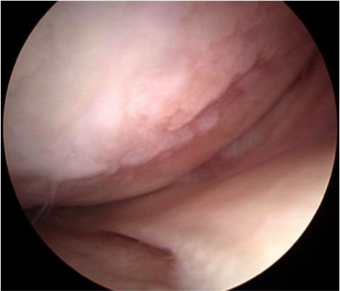

関節鏡視下手術

関節鏡という内視鏡のカメラを膝関節内に挿入(約1cmの創、2~3箇所)し、テレビのモニターを見ながら関節内を観察し、同時に手術も行います。関節内の軟骨、半月板、靭帯などの状態を観察し、半月板の損傷があれば半月板切除術、滑膜炎が認められれば滑膜切除術を行います。また、直視下に軟骨の状態(変形性関節症の有無や程度)の評価はできますが、変形性関節症による軟骨の損傷に対しては例外を除いて関節鏡視下手術では有効な治療法は現在のところありません。麻酔は通常腰椎麻酔(下半身麻酔)で行い、1時間くらいの手術です。関節鏡クリニカルパスという入院治療計画に沿って行い、入院期間は1週間以内です。

内側半月板損傷

半月板切除後

内側の軟骨は高度に欠損している(左:関節鏡所見)。